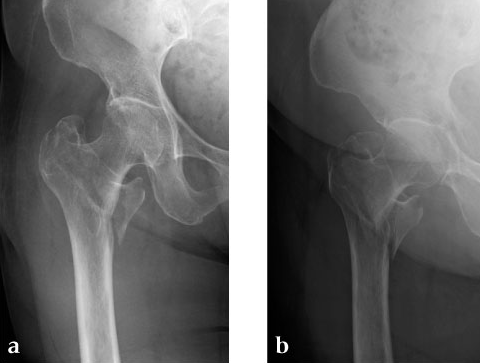

A 78-year-old Japanese patient fell while at her home and sustained an AO 31-A2.1 injury (see Fig 5).